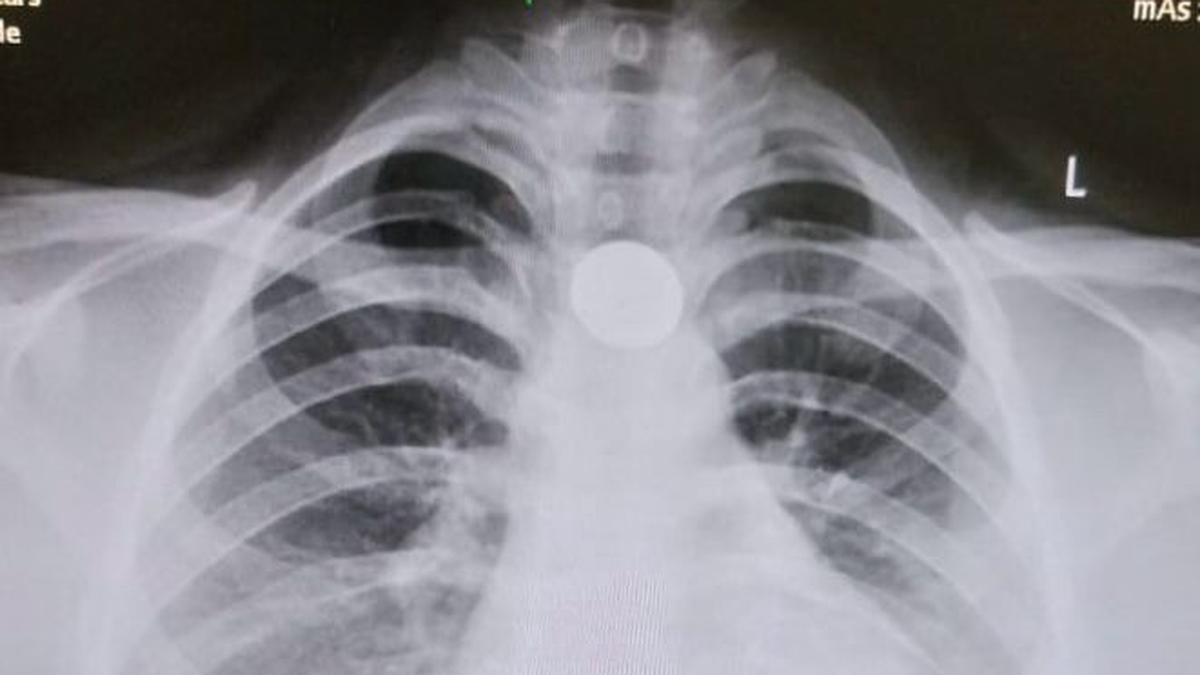

“Some items need urgent removal, especially button batteries, which can burn through tissue rapidly due to electric discharge. Coins stuck in the oesophagus also require removal if they cause symptoms,” says Dr. Kesavelu , citing the 2023 ESPGHAN guidelines (European Society for Paediatric Gastroenterology Hepatology and Nutrition), which outline detailed protocols for ingestion emergencies.